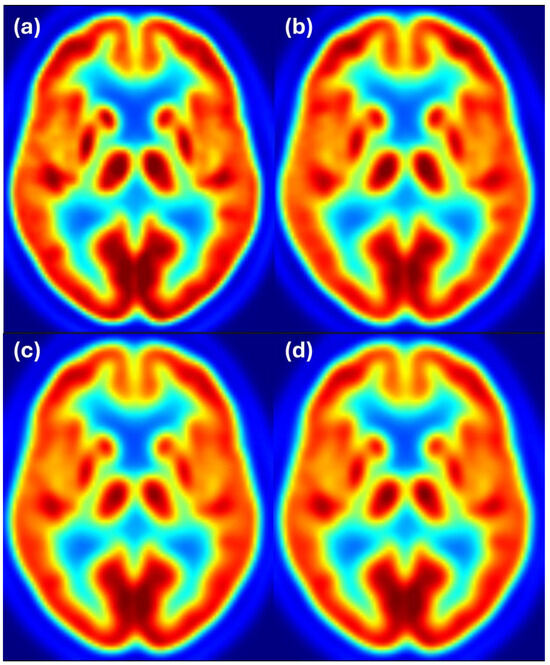

Figure 7 shows axial slices for the 8 mm target resolution for HR+ matching HRRT resolution. Also, here, the HR+ image after filtering with the estimated filter follows the reference image at 6 mm resolution, while the differences between the HR+ and HRRT images at 8 mm resolution are hardly noticeable. Color scale indicates FDG uptake levels: red for high, green/yellow for medium, and blue for low uptake.

Figure 7. Harmonization results for the HR+ scanner matching the HRRT images filtered to 8 mm resolution. Image (a) shows the unfiltered HR+ image, (b) shows the HRRT image at the target resolution of 8 mm, (c) shows the HR+ image after filtering with the estimated filter, and (d) shows the HR+ image filtered to 8 mm resolution. Color scale indicates FDG uptake levels: red for high, green/yellow for medium, and blue for low uptake.